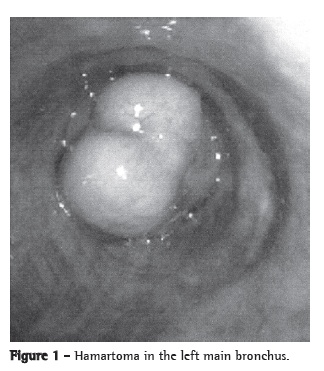

A 32-year-old female patient presented with recurrent pneumonia in the left lower lobe. During the clinical investigation, a chest X-ray showed atelectasis of the left lower lobe. Chest CT scans showed a lesion that partially obstructed the left main bronchus. Flexible bronchoscopy showed an elevated lesion, with a bosselated pink surface and a pedicle on the medial wall of the left main bronchus, blocking 90% of its lumen, as well as a large amount of purulent secretion distal to the lesion (Figure 1). The histological examination of the biopsy specimen was compatible with hamartoma. Systemic antibiotics were administered for one week prior to endoscopic intervention. The lesion was uneventfully excised using a flexible bronchoscope, a polypectomy snare, and electrocautery. There was complete opening of the bronchial lumen, as well as good clinical and radiological evolution (Figure 2). There were no clinical signs of recurrence 15 months after the procedure.